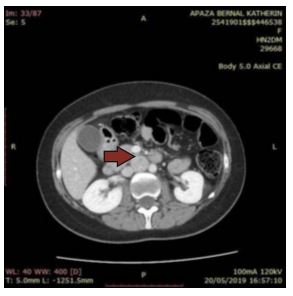

Subsequently, a contrast-enhanced abdominal CT scan was performed, revealing a solid mass with well-defined borders located in the retroperitoneal intercaval region, immediately anterior to the L2-L3 intervertebral disc, measuring 26 x 23.9 x 28.8 mm. The mass showed intense enhancement with contrast administration, suggestive of a retroperitoneal paraganglioma (Figures 1 and 2).

Figure 1. Abdominal CT scan showing a solid mass with defined borders located in the retroperitoneal intercaval region

Figure 2. Abdominal CT scan showing intense enhancement after contrast administration, suggestive of a retroperitoneal paraganglioma